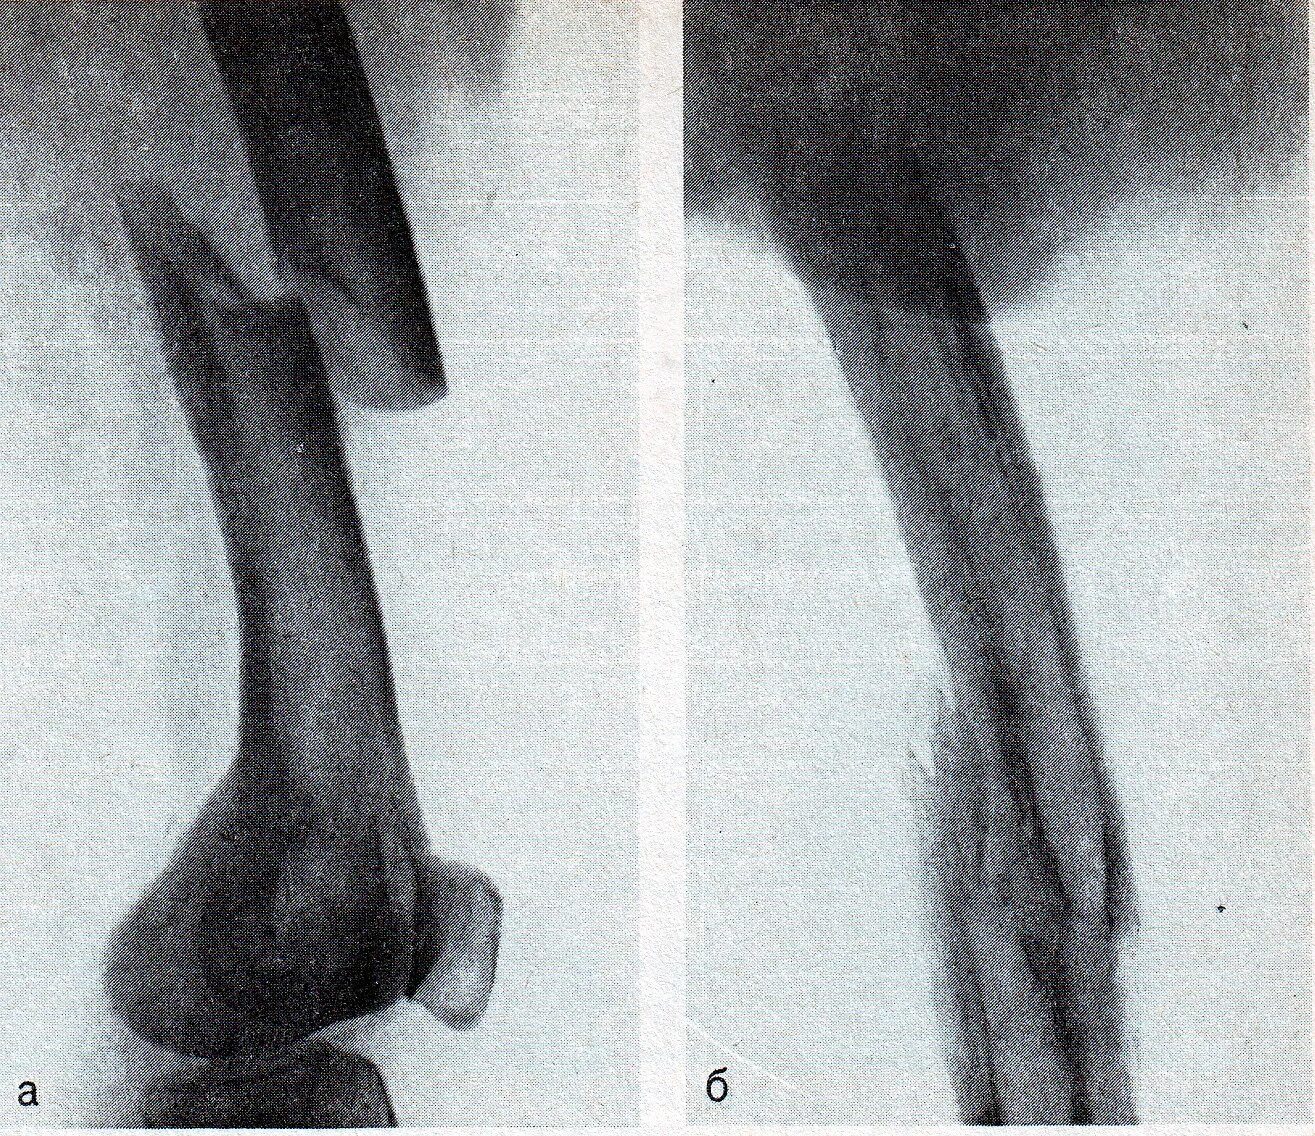

Перелом 1 3 бедра